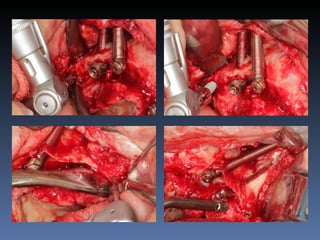

BOX 1

Diagnóstico: Desdentada total maxila

BOX 1 Maura GraçaMontereiro Idade – 59 anos Sexo – Feminino Raça – Caucasiana ASA – II Data- 27-04-2012 Diagnóstico: Desdentada total maxila já reabilitada com “All-on-four” híbrido; periimplantite dos implantes anteriores. Plano de tratamento: Remoção dos implantes anteriores, instalação de dois implantes Zigomáticos e dois implantes posteriores na tuberosidade.